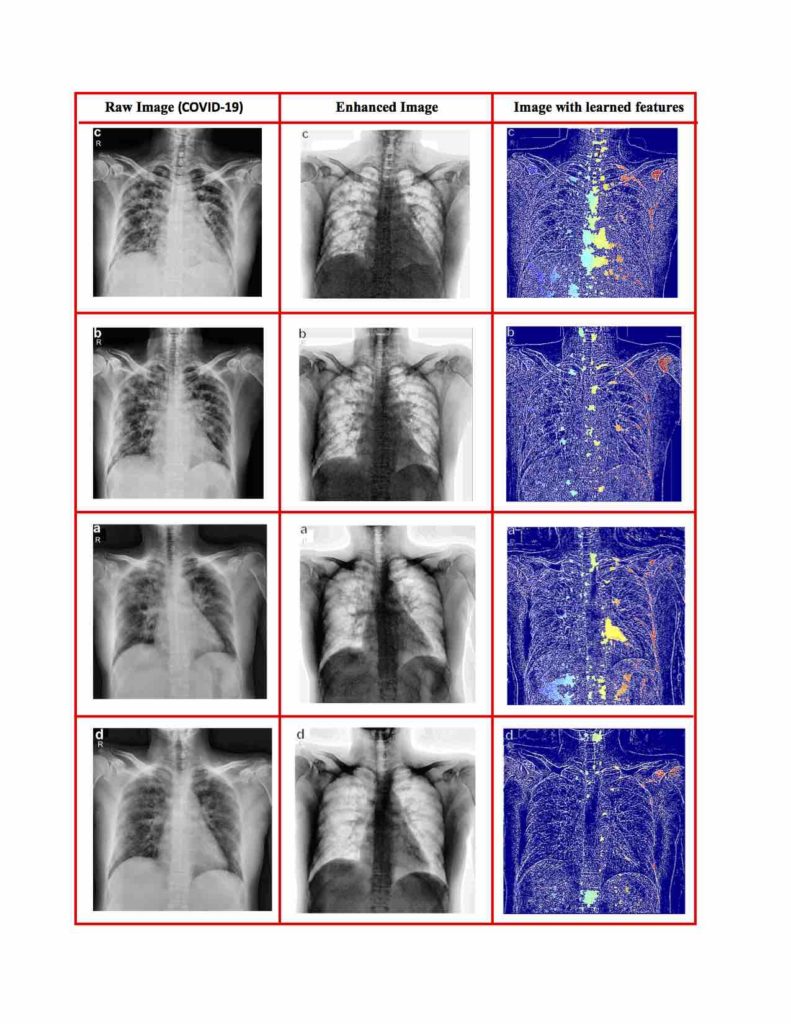

Image processing techniques enhance the targeted X-ray images and use an algorithm to create visual cues related to each particular disease.

“A tailor-made AI algorithm scans enhanced images and then extracts visual cues to help automatically identify coronavirus cases and monitor the development of the virus in infected people,” said Professor Abdul Sadka.

It uses multiple layers of information processing to automatically build a picture of what to look for in X-rays, then trains a deep learning model to classify the type of the disease.